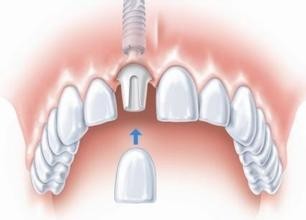

美牙冠:美牙冠具有修复牙齿不拔牙、不伤牙等优点,美容冠技术自从被引进康贝佳,被广泛应用深龋患者可以保护原牙,且不着痕迹。美牙冠的价格一般在几千元左右。

康贝佳美牙冠技术:

自然通透:色泽自然,通透不反白,晶莹亮丽。

准确密合:口腔全景机全方位扫描,智能精细设计,降低磨牙量,保障密合效果。

坚固耐用:采用仿生材料,无异物感,舒适耐磨,坚固抗压,耐用使用寿命更长久。